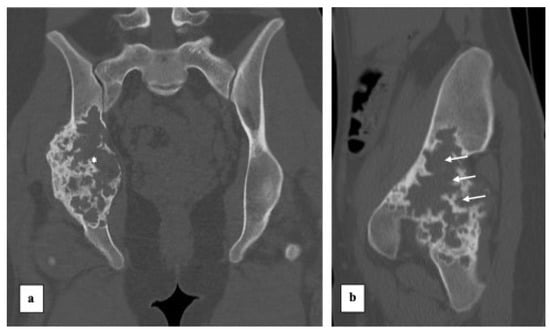

2. Case Presentation